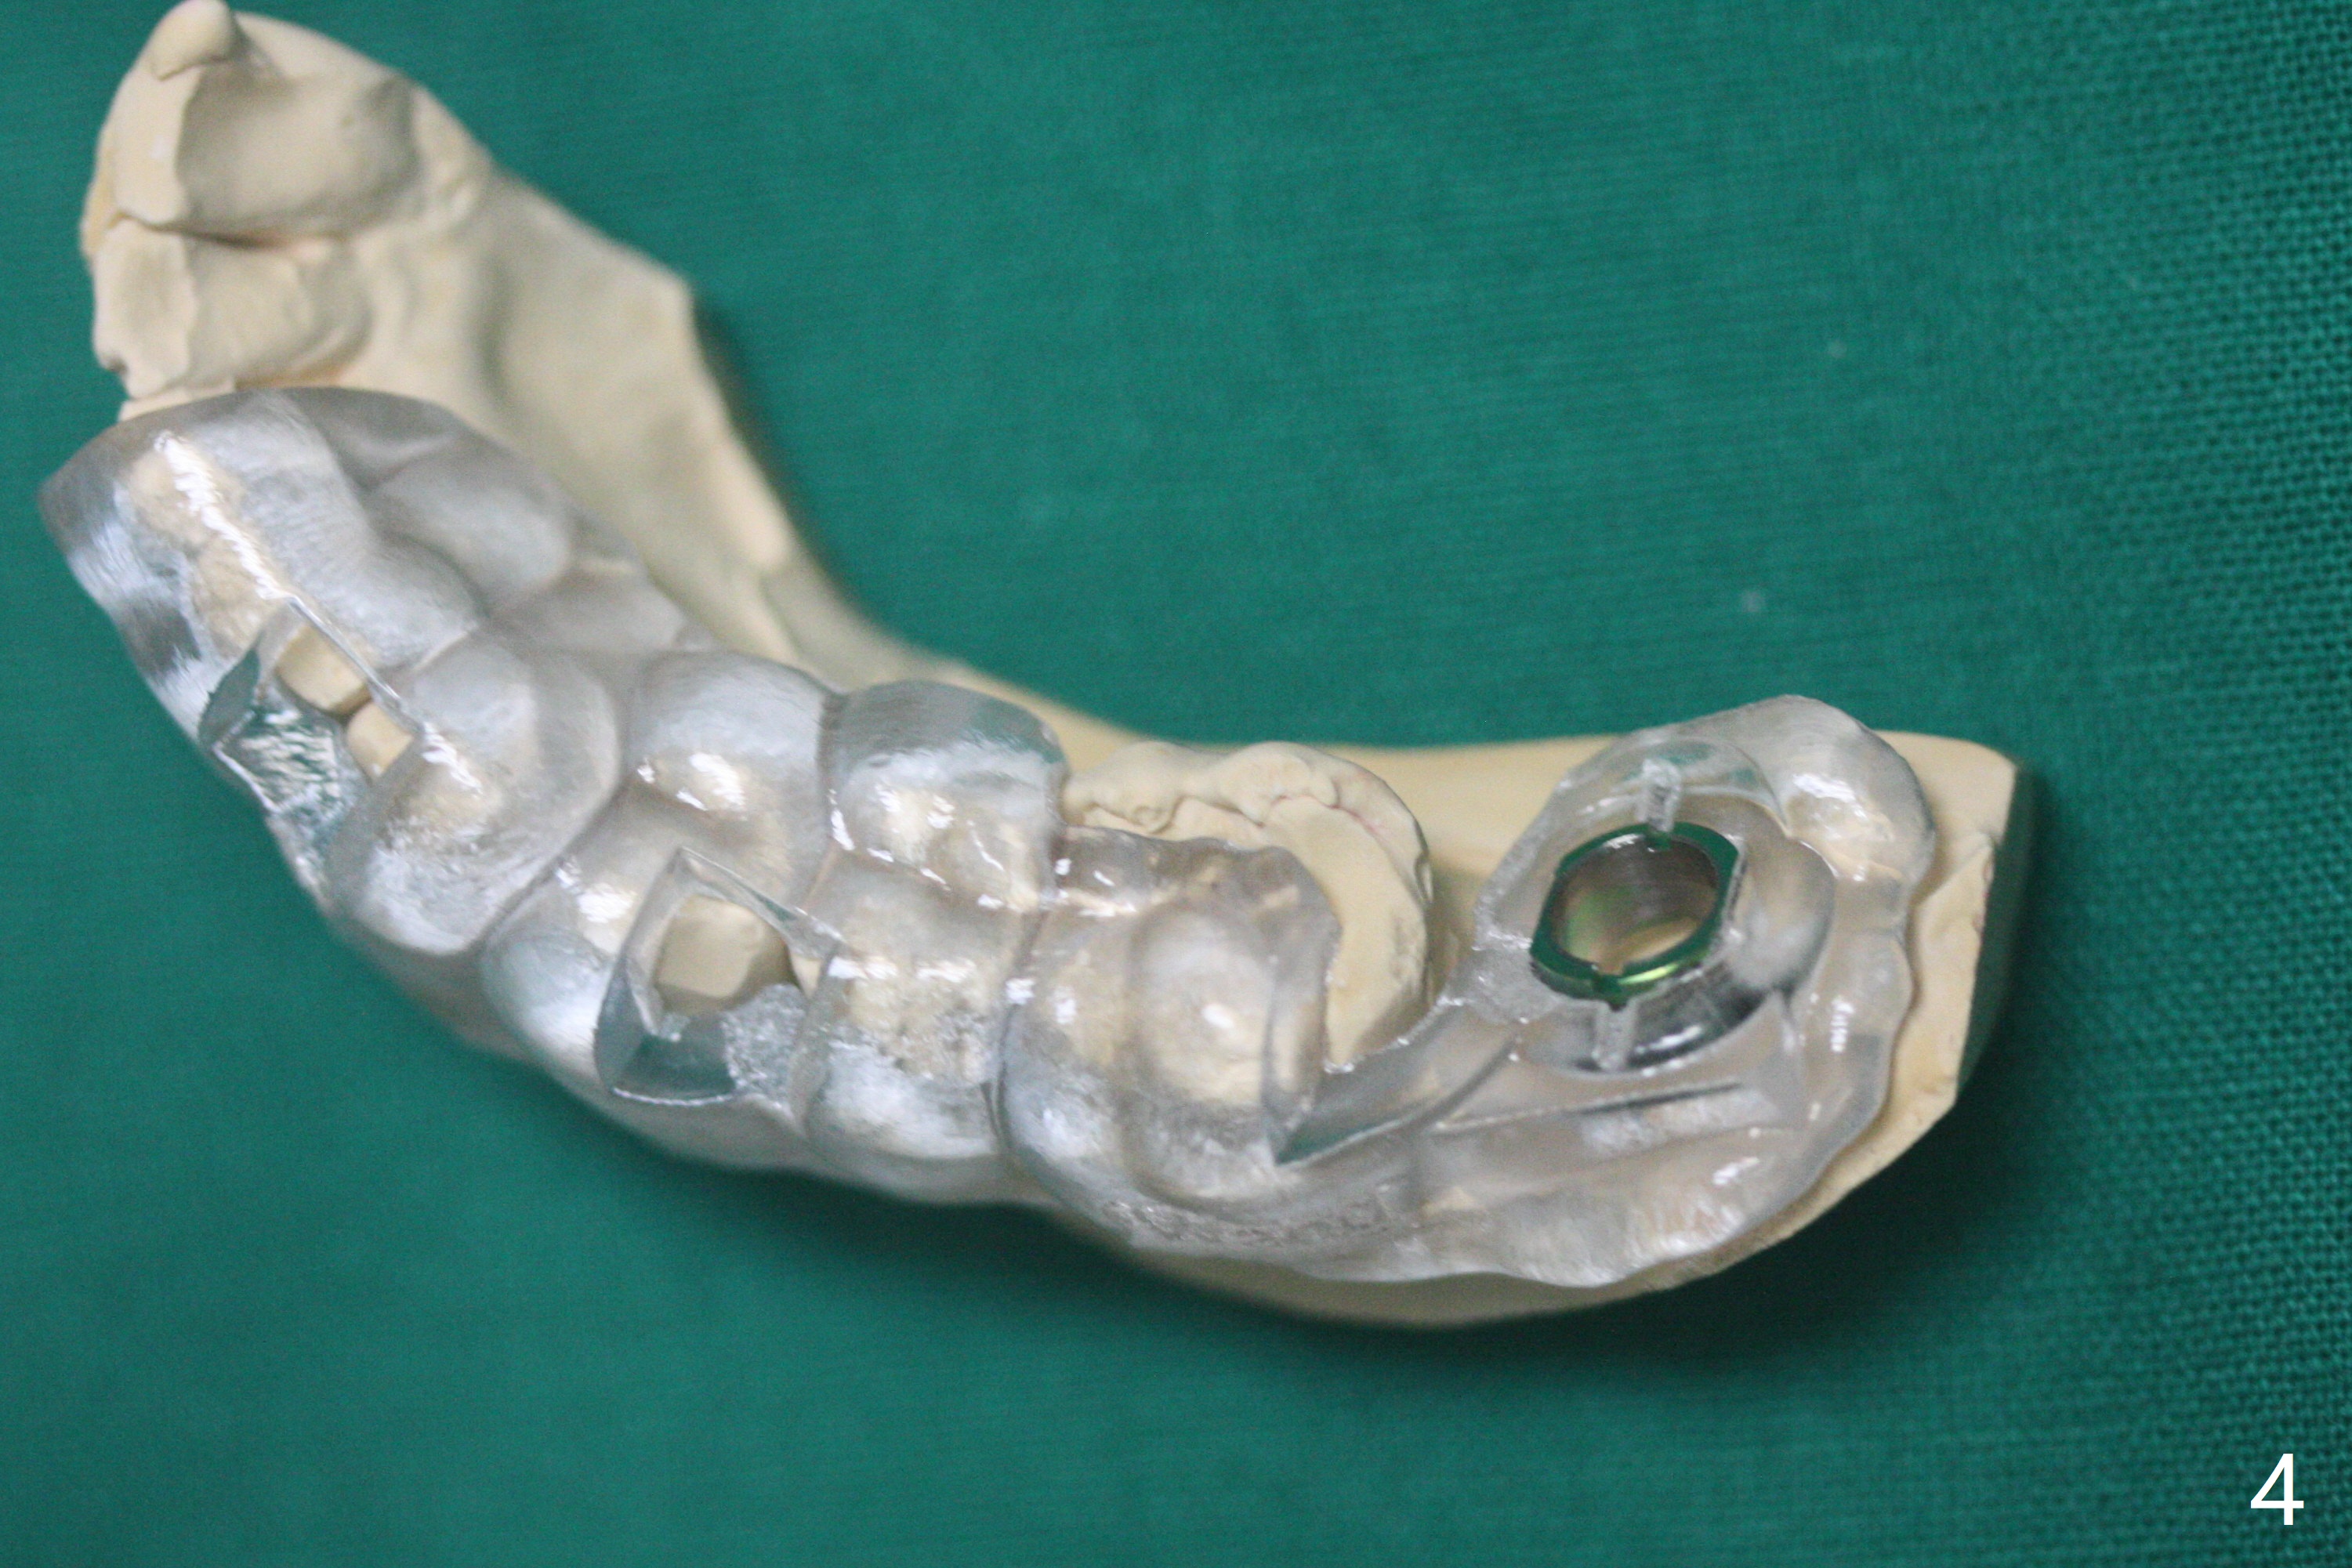

病人舌头大,取模时19号牙舌侧不全(图三),导板制作就没有覆盖舌侧(图四),导板向舌侧倾斜,不准确,植牙就太偏颊侧(图一)。取出植体还必须做近中颊侧切口,放置粘性骨粉和PRF膜(图二:*),PGA缝合,牙周胶水。